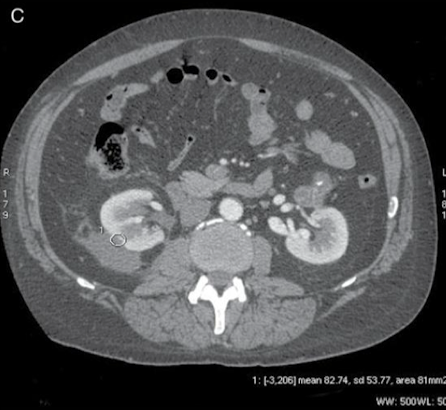

Why is this ROI not appropriate?

Measuring contrast enhanced kidney with non-contrast enhanced tissue → SD = 53.77